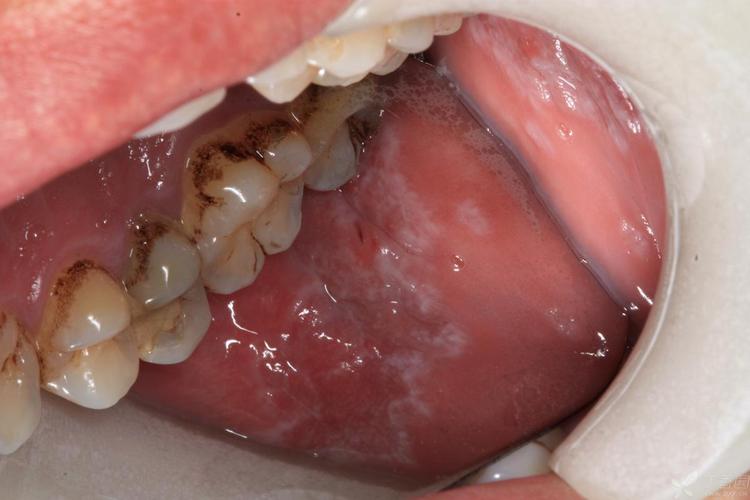

(图片来源网络,侵删)

- 网状型(最常见): 口腔黏膜上出现白色、灰白色的条纹,交织成网状、线状或环状,看起来像蕾丝花边,常见于颊黏膜(内侧脸颊)、舌背、牙龈等部位。

- 糜烂型(最严重): 在白色条纹的基础上,出现充血、糜烂、溃疡,有明显疼痛感,尤其在进食辛辣、酸性食物时加剧,这种类型有癌变风险,需要特别警惕。

- 其他类型: 包括丘疹型、斑块型、萎缩型等。